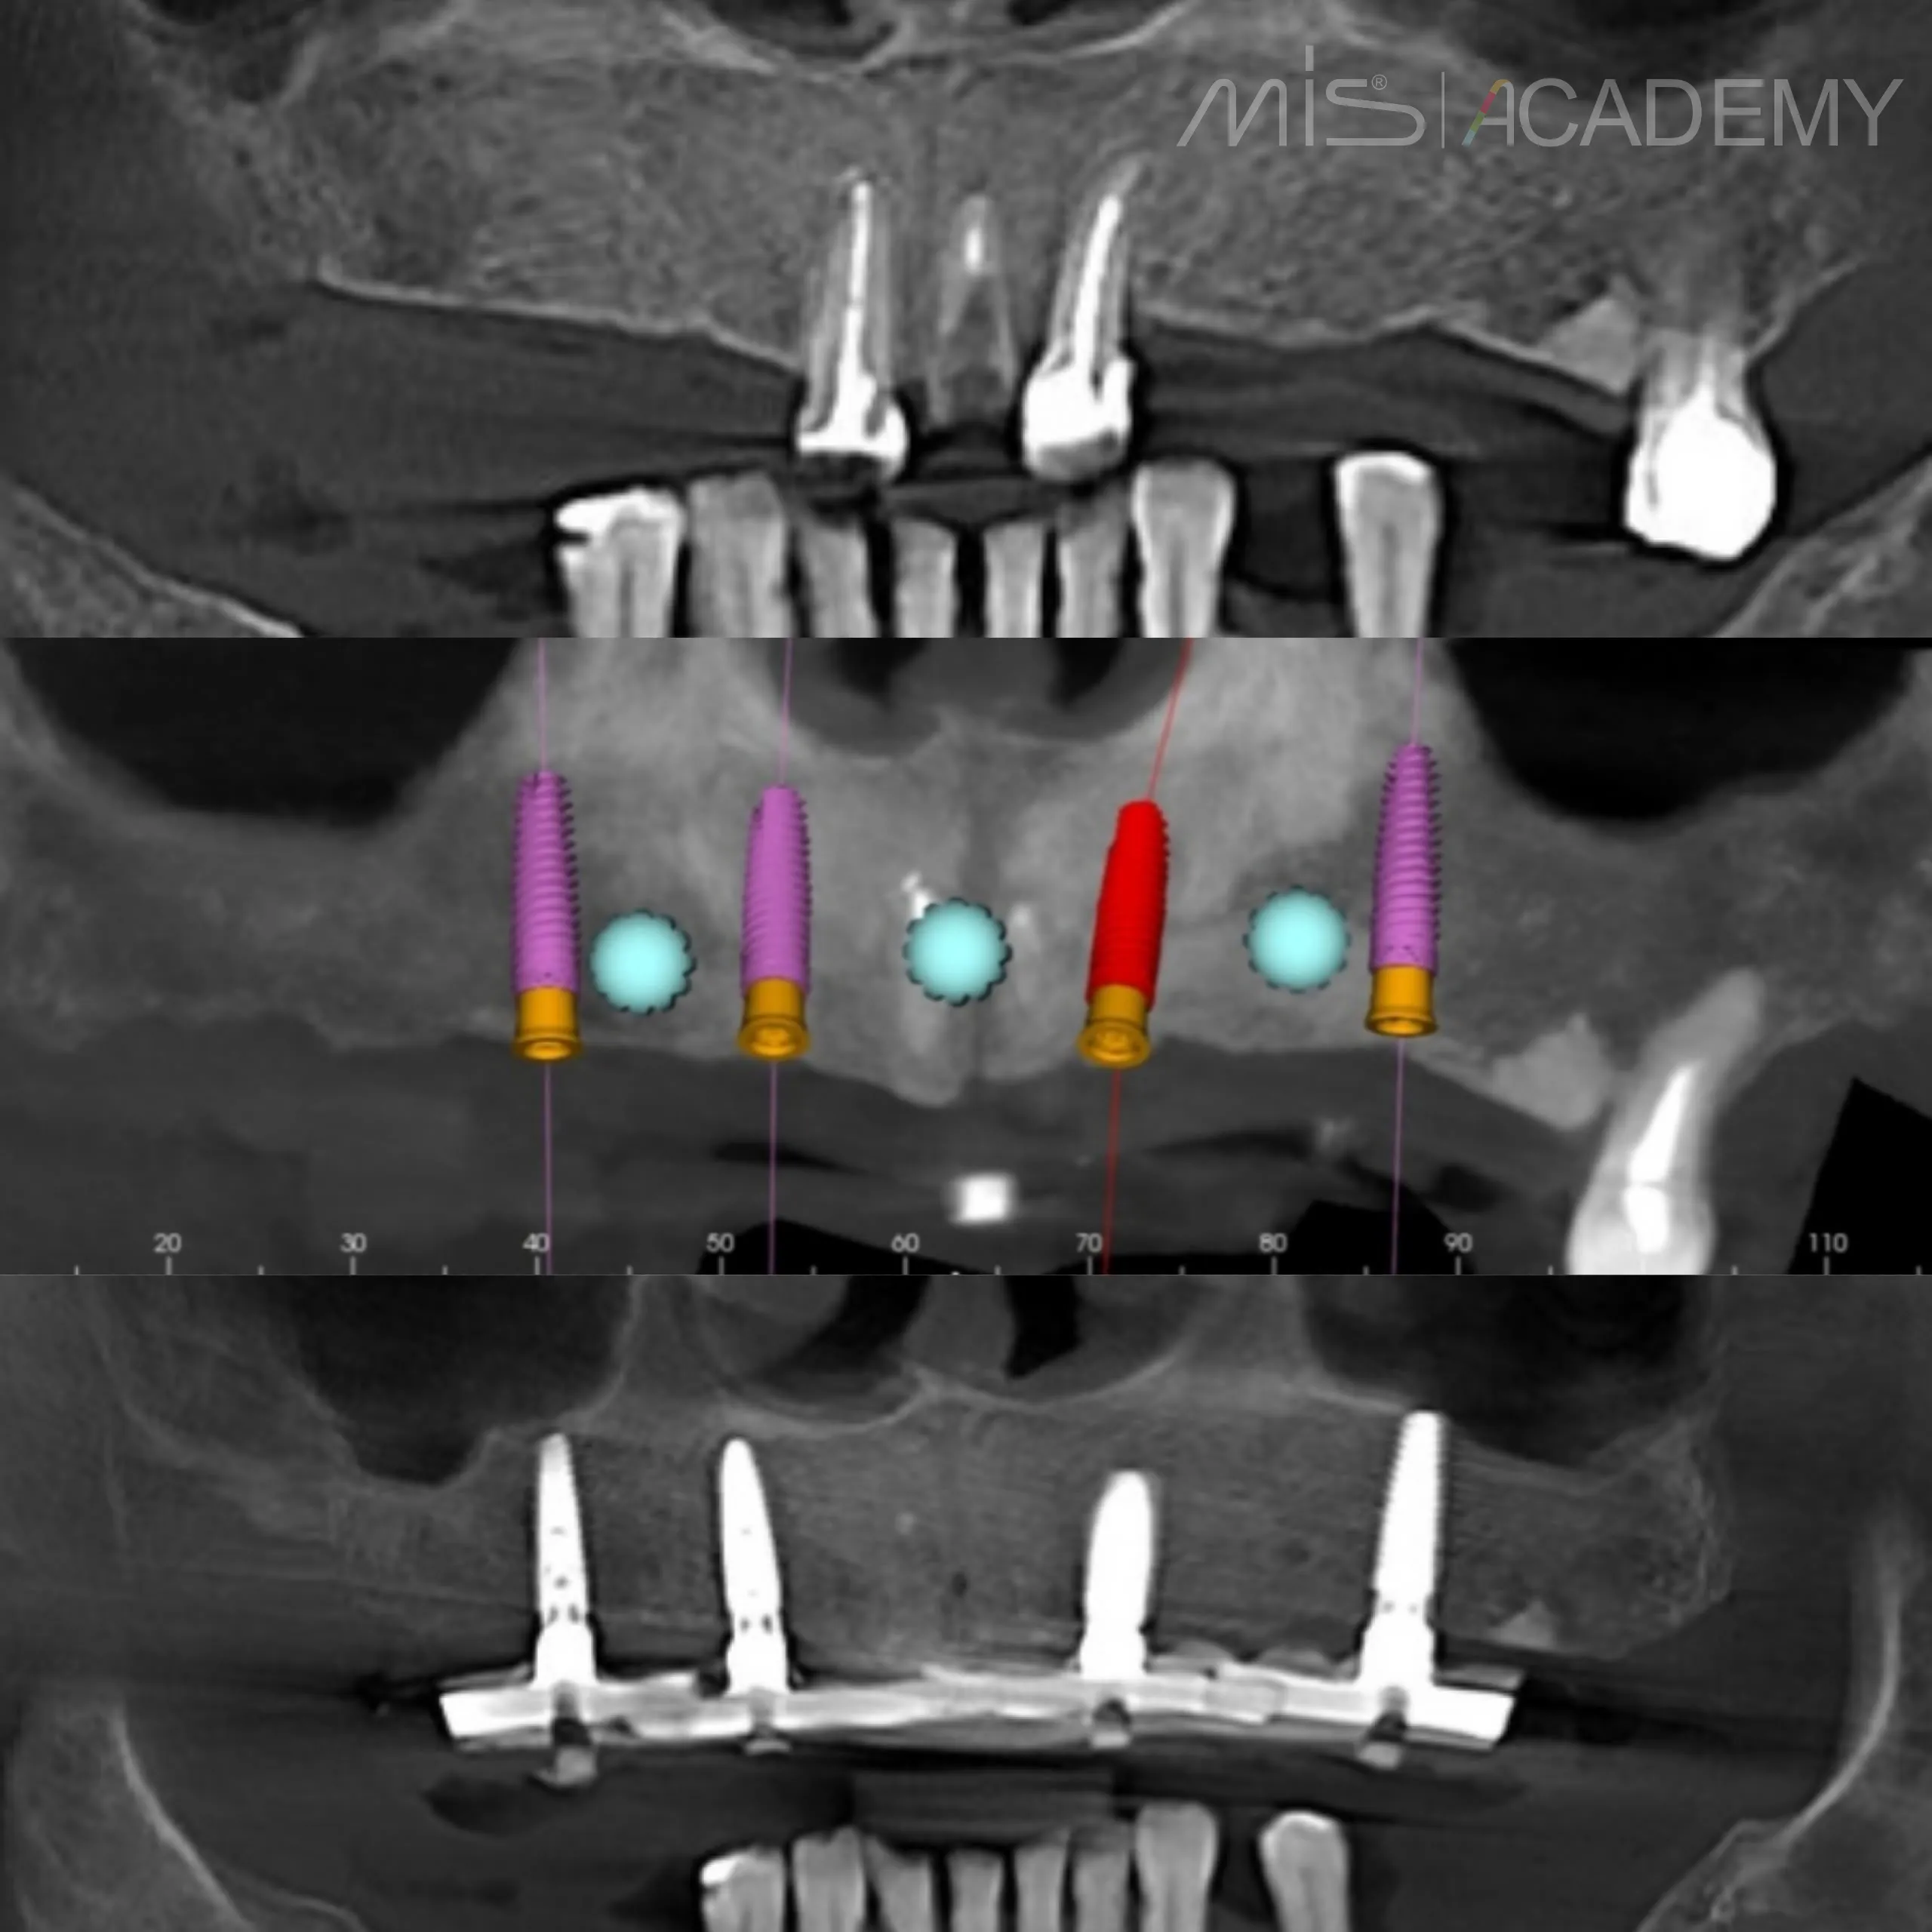

Пациент 64 года, стоматофобия + очень ярко выраженный языкоглоточный рефлекс.

(Пока решились только на верх).

— 4 имплантата MIS C1 + 4 connect-абатмента.

— IDR в области 22.

— Несколько СДТ.